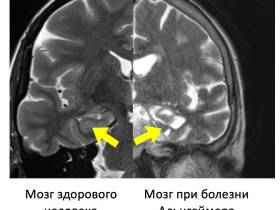

Болезнь Альцгеймера относится к группе нейродегенеративных заболеваний, при которых происходит прогрессирующая гибель нейронов. В основе развития болезни Альцгеймера лежит в первую очередь уменьшение объема гиппокампа – отдела головного мозга, который отвечает за память человека. Он становится рассеянным, забывает те события, которые происходили совсем недавно. Однако пациенты прекрасно помнят прошлое: имена друзей детства, события и даты. Родственники уверены, что раз прошлое близкий хорошо помнит, то значит всё в порядке. Это, наоборот, должно насторожить.

Что происходит с мозгом человека при болезни Альцгеймера

– Нарушения памяти связаны с уменьшением количества клеток в гиппокампе, который расположен под корой головного мозга. В свою очередь гибель нейронов происходит вследствие накопления аномальных белков – бета-амилоида и тау-протеина. Функции нейронов заключаются в генерировании и передаче нервных импульсов, обработке и хранении поступающей информации.